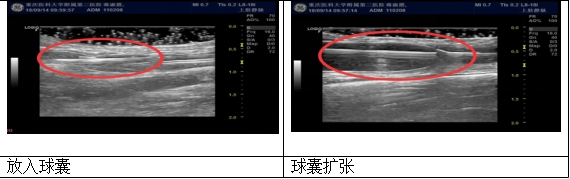

PTA球囊扩张术就是在超声引导下,通过皮肤表面穿刺血管,送入球囊扩张导管对血管的狭窄部位进行扩张,或者对血管的狭窄部分进行扩张,或者对血栓形成部分进行血栓压迫,使狭窄部分矫正达到或大于正常血管内径,是目前治疗动静脉内瘘狭窄的最新技术。

超声可以实时显示血管腔及导丝、球囊导管的进行情况减少血管穿孔等并发症。